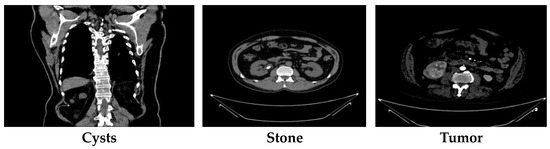

Nazmul Islam and Humaion Kabir [24] compiled the CT kidney dataset using the picture archiving and communication system (PACS) from several hospitals in Dhaka, Bangladesh. Some hospitals in Dhaka serve a wide variety of urban communities. Given that Dhaka is a highly populated and culturally diverse city, the dataset probably includes people from different socioeconomic statuses, enhancing its ability to represent urban patients in Bangladesh. This dataset includes images of patients with normal kidneys, tumors, stones, or cysts. The dataset includes coronal and axial cuts from both non-contrast and contrast urogram and abdomen CT scans, totaling 12,446 images—normal: 5077 CT images; cyst: 3709 CT images; stone: 1377 CT images; and tumor: 2283 CT images. Each CT image was sized 512 × 512 pixels. The dataset can be found on Kaggle, and its class distribution is shown in Table 3. The CT images were originally in DICOM format but were converted to JPEG using the Sante Dicom tool. The CT images were annotated using the Philips IntelliSpace Portal application and were double-checked by a medical professional and technician to ensure accuracy. Figure 1 depicts a sample of CT images from this CT kidney dataset.

In our experiment, we considered ethical matters. While the dataset description does not explicitly mention ethical approvals or consent, it is generally understood that open-source datasets comply with ethical guidelines. Consent for the use of de-identified data is typically obtained from patients during the data collection phase. For datasets collected and shared on platforms like Kaggle, the responsibility for ensuring compliance with privacy regulations usually falls on the data provider.